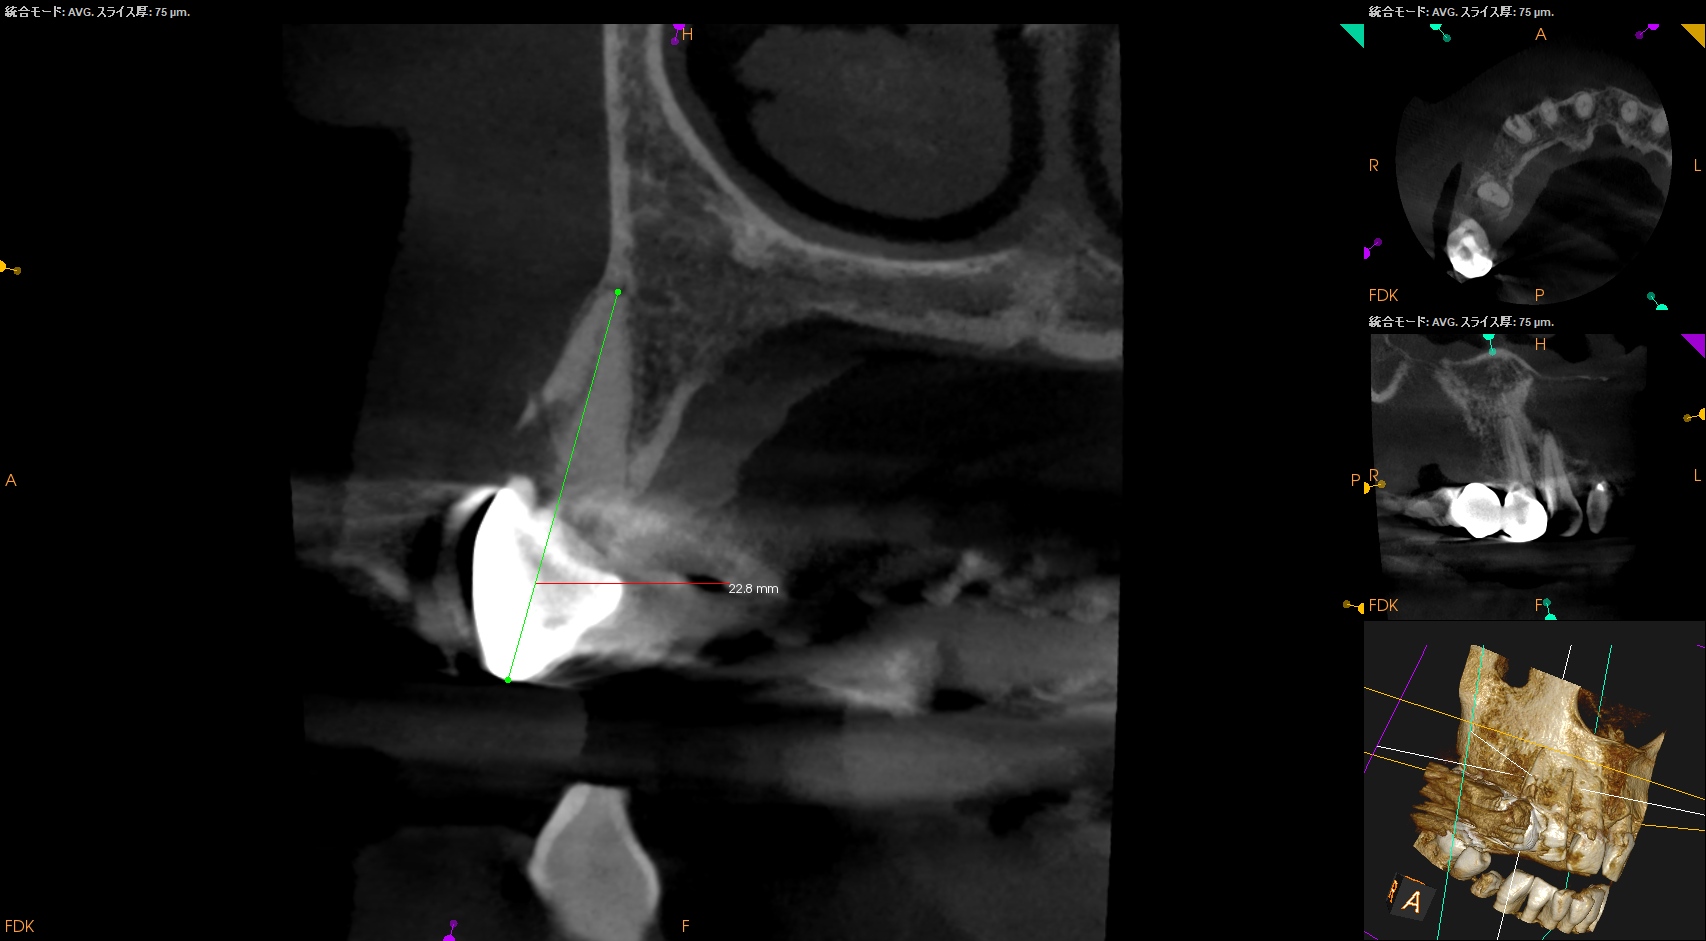

また根管治療する際は、

RIL(Radiographic Instrumentation Length)は23mm程度であるが、

クラウンの切端に穴を開けて根管治療をしなければならず、これは現実的には無理だろう。